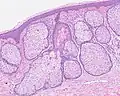

Sebaceous hyperplasia in 55-year-old woman. Diagnosis was histologically verified.

Sebaceous hyperplasia shares histopathological similarities with the typical architecture of the folliculosebaceous unit, but with larger and expanded sebaceous glands.[12][13]